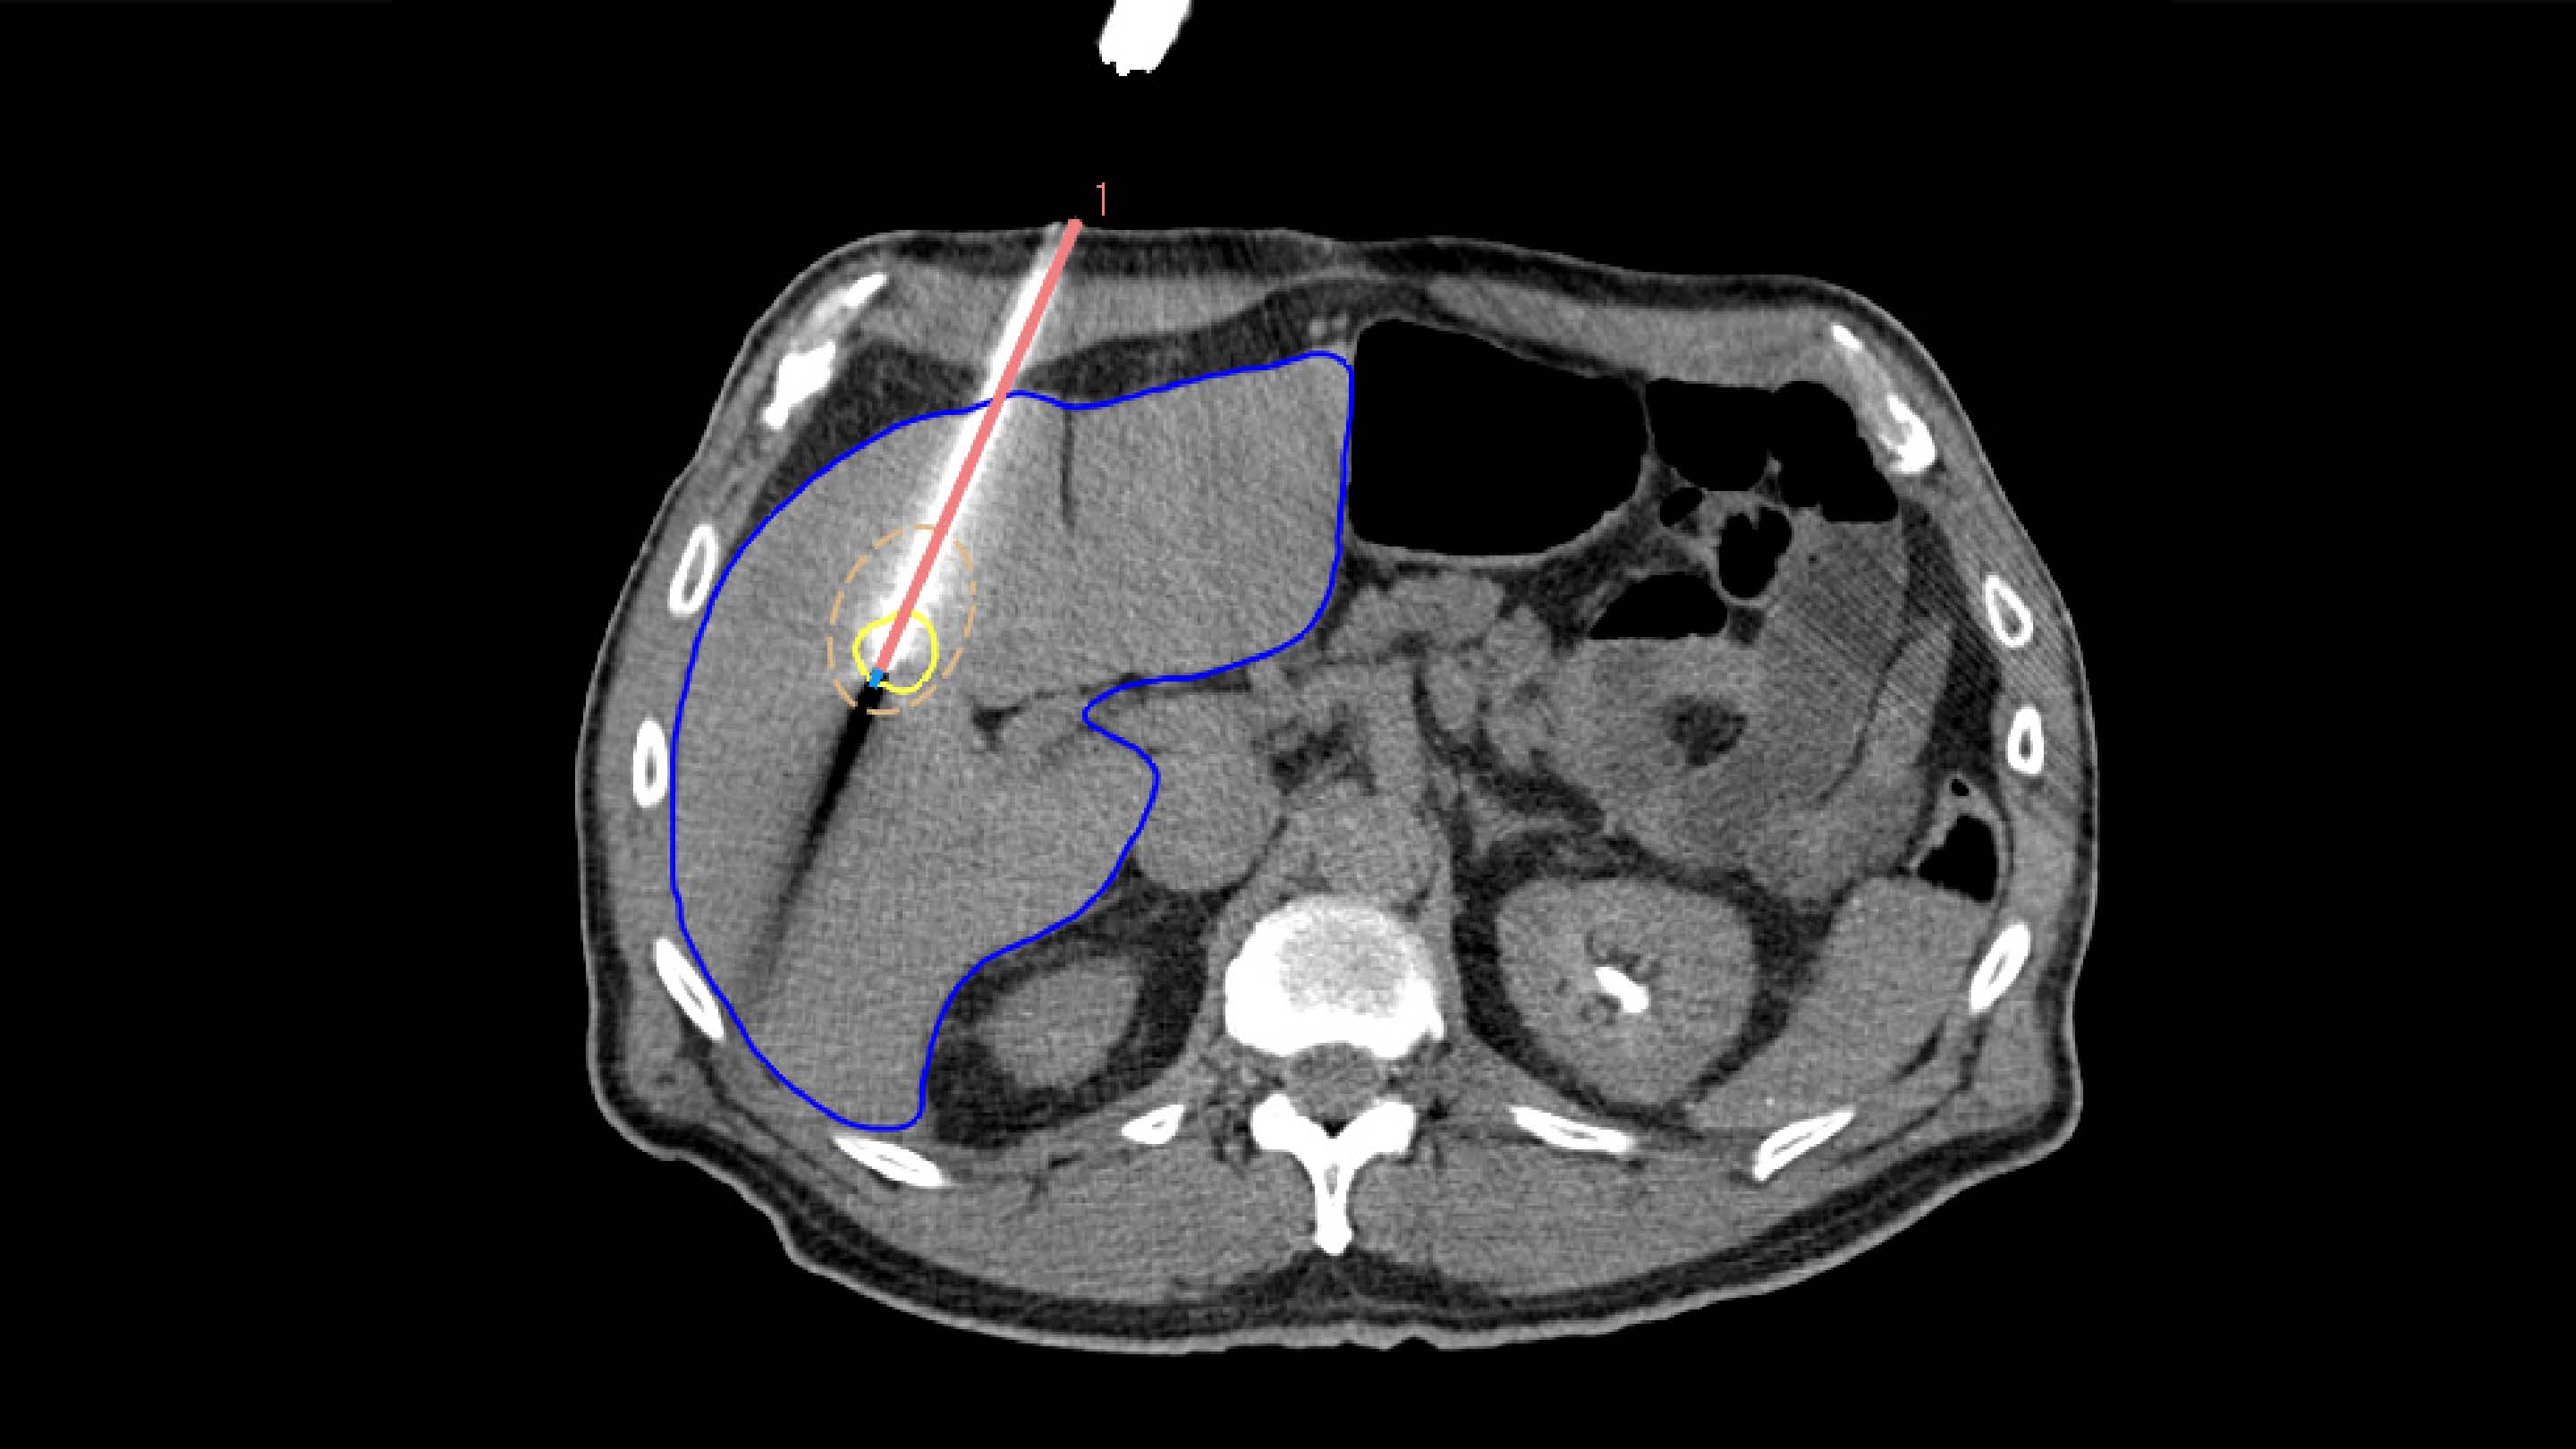

2. TARGETING

To ensure accurate applicator placement before treatment, the segmented tumors from the planning phase are mapped using deformable registration, allowing for a visualization of the anticipated tumor position. Additionally, the ablation zone can be estimated based on the applicator parameters, such as its current position, selected power, and ablation duration.